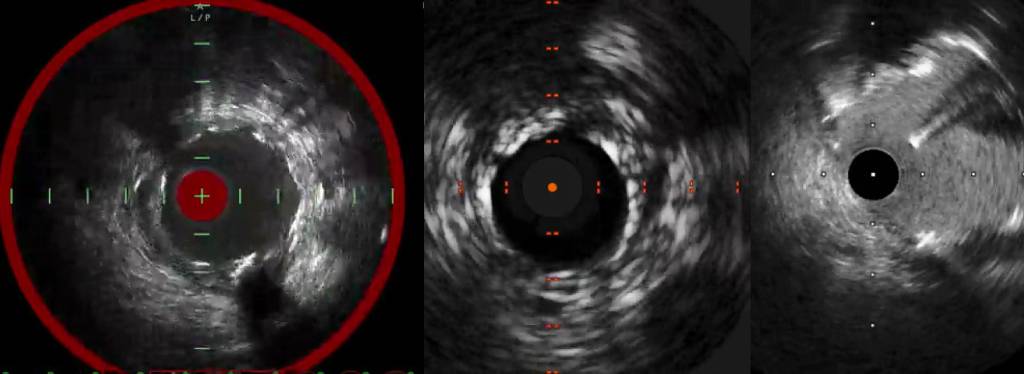

- (1Α) Φυσιολογική απεικόνιση αγγείου σε IVUS. Διακρίνονται οι 3 χιτώνες, έσω χιτώνας (intima) (πράσινο βέλος), μέσος χιτώνας (media – EEL) [ηχοδιαυγαστικός μαύρος δακτύλιος (κόκκινο βέλος)] και έξω ινώδης χιτώνας (adventitia) (μπλε βέλος).

- (1Β) Απεικόνιση έκκεντρης αθηρωματικής πλάκας σε IVUS (περιοχή εντός πορτοκαλί πλαισίου). Παρατηρούμε τη διεισδυτική ικανότητα του IVUS που επιτρέπει την ακριβή εκτίμηση του πάχους της αθηρωματική πλάκας.

- (1C) Φυσιολογική απεικόνιση αγγείου σε OCT. Διακρίνονται οι 3 χιτώνες, έσω χιτώνας (intima) (πράσινο βέλος), μέσος χιτώνας (media – EEL) [ηχοδιαυγαστικός μαύρος δακτύλιος (κόκκινο βέλος)] και έξω ινώδης χιτώνας (adventitia) (μπλε βέλος).

- (1D) Απεικόνιση έκκεντρης αθηρωματικής πλάκας σε OCT (περιοχή με βέλη). Παρατηρούμε τη χαμηλή διεισδυτική ικανότητα της OCT που δεν επιτρέπει την ακριβή εκτίμηση του πάχους της αθηρωματική πλάκας (απορρόφηση φωτός). Αντιθέτως, η υψηλή ευκρίνεια επιτρέπει την αναγνώριση δομών όπως μακροφάγα (κοκκία με υψηλή φωτοαντανάκλαση –light backscattering) (κόκκινα βέλη).